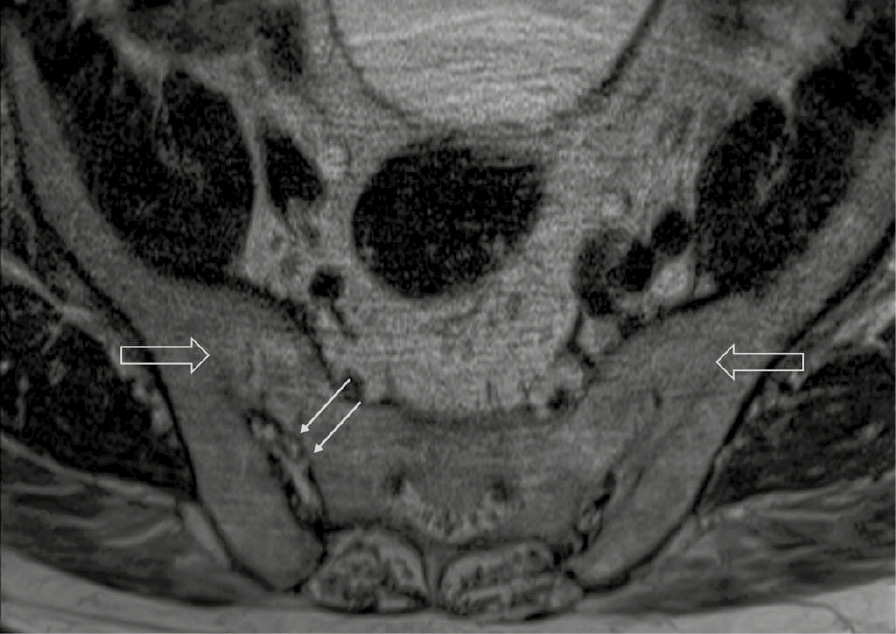

При компьютерной томографии органов грудной клетки данных за «свежие» очаговые и инфильтративные изменения не получено. Увеличения лимфатических узлов подмышечных областей, средостения, корней легких не выявлено. Отмечался усиленный грудной кифоз, обызвествление передней продольной связки, на всем уровне исследования определялись передне-боковые спондилофиты, а также анкилоз большинства реберно-поперечных суставов. По данным рентгенографии кистей (рис. 1, 2) и стоп (рис. 3, 4) диагностированы признаки эрозивного артрита, анкилоз суставов запястья. По данным МРТ крестцово-подвздошных суставов (КПС) определялся неравномерный анкилоз КПС, хрящи по суставным поверхностям неравномерной толщины, примерно на половине протяжении сустава отсутствуют, «суставной промежуток» облитерирован. Неравномерность и нечеткость контура суставных поверхностей за счет множества краевых эрозий справа, единичных – слева, с наличием остеокластоза, в нижнем отделе слева по смежным отделам определяются участки трабекулярного отека, данная находка клинически интерпретирована как двусторонний активный сакроилиит (рис. 5, 6).

Рис. 5. Магнитно-резонансная томография (Т2-взвешенное изображение в поперечной проекции). Протяженные участки анкилоза крестцово-подвздошных сочленений (толстые стрелки), эрозии суставных поверхностей (тонкие стрелки)

Рис. 6. Магнитно-резонансная томография (Т1-взвешенное изображение в косой корональной проекции). Протяженные участки анкилоза крестцово-подвздошных суставов (толстые стрелки), субхондральная киста правой латеральной массы крестца (тонкая стрелка). При магнитно-резонансной томографии крестцово-подвздошных сочленений с обеих сторон определяются крупные зоны анкилоза (суставные щели полностью облитерированы на 1/3 поверхности сустава справа, на 2/3 поверхности слева, что соответствует III рентгенологической стадии сакроилиита справа, IV стадии слева по Келлгрену). На остальных участках суставной хрящ неравномерно истончен, суставные поверхности неровные за счет множественных эрозий справа, единичных – слева. Определяются единичные мелкие (4 мм) субхондральные кисты справа